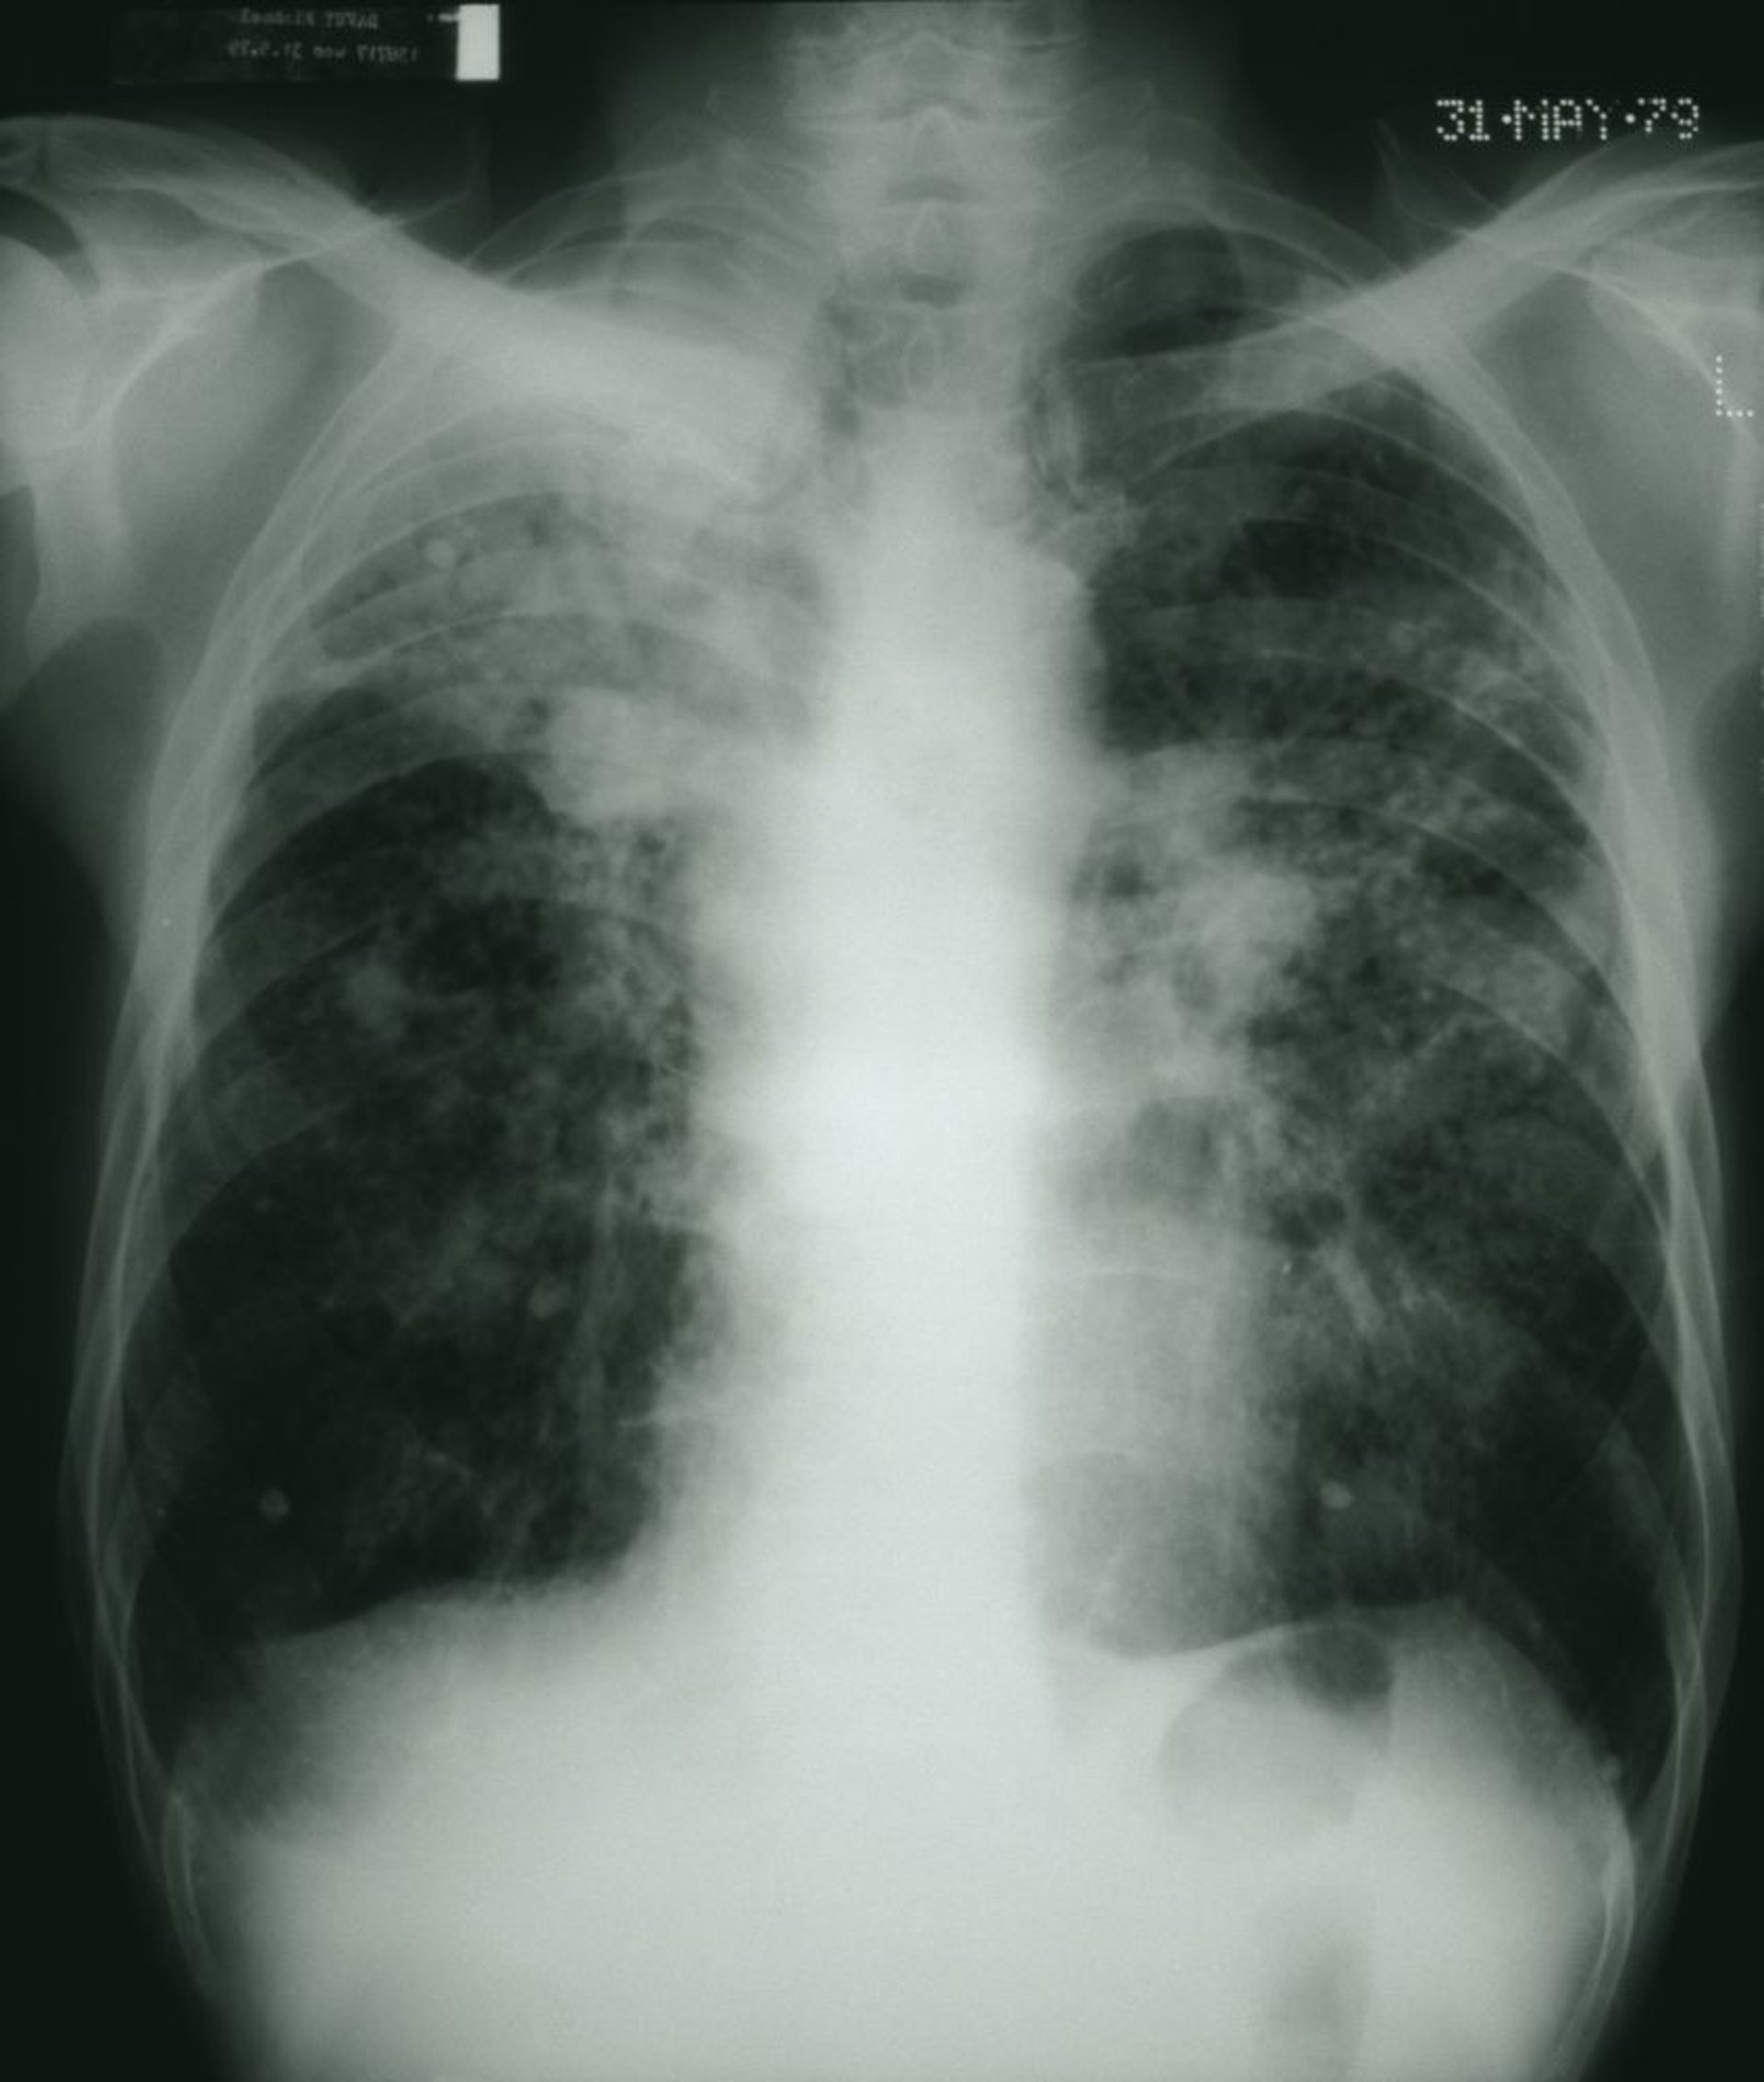

As áreas pulmonares escuras mostram um aspecto mosqueado com placas de massas fibrosas brancas consistente com pneumoconiose avançada do trabalhador de carvão.

STEVE ALLEN/SCIENCE PHOTO LIBRARY